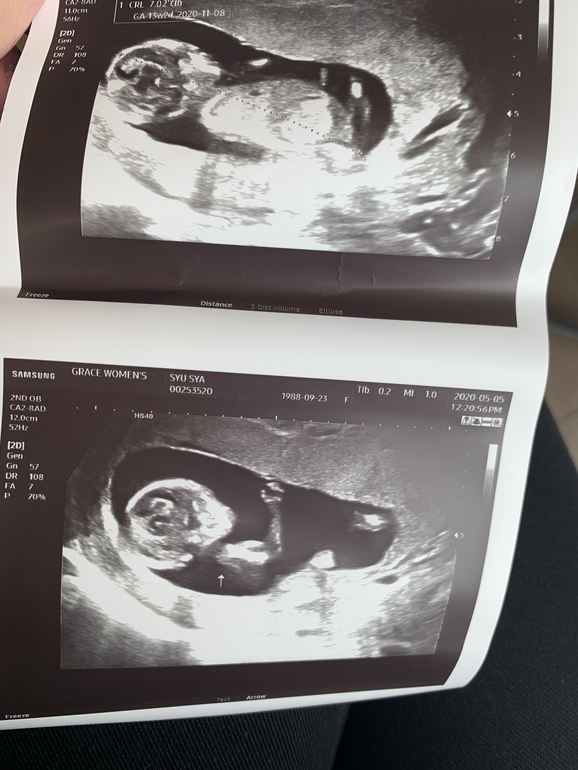

До 11 недель ходили в одну клинику, а сейчас решили поменять. Пришли на УЗИ, и врач очень уверено говорит, что мальчик. Даже фото показал🙈😅 Вот теперь думаю, насколько это точно.

По остальным параметрам, вроде, всё хорошо.